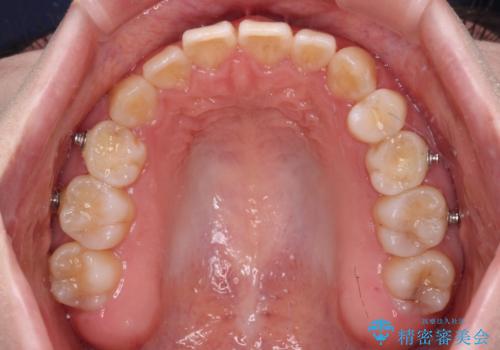

ディープバイトをインビザライン矯正で改善

- 前歯のデコボコと強い咬みしめを気にして来院された患者様です。

インビザラインを用いて、前歯の叢生を解消するとともに、ディープバイトを改善していくこととしました。

上顎に乳歯が左右1本ずつ残っていたため、若干咬み合わせに不具合が残りましたが、強い咬合力の原因であったディープバイトをしっかりと改善することができました。